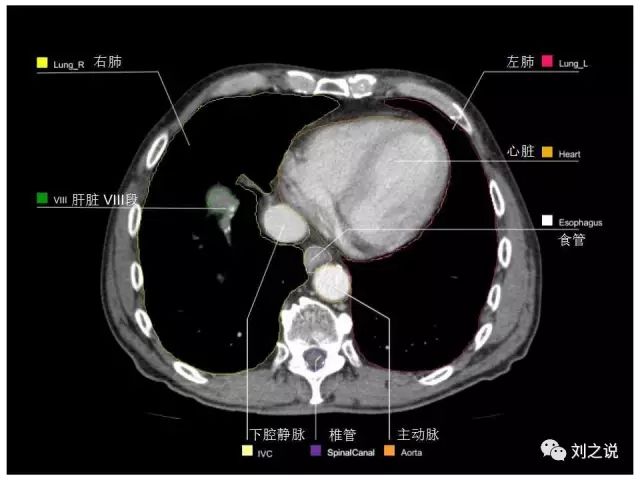

【解剖】高清实用 腹部CT断层

参考RTOG共识和3D-body解剖。